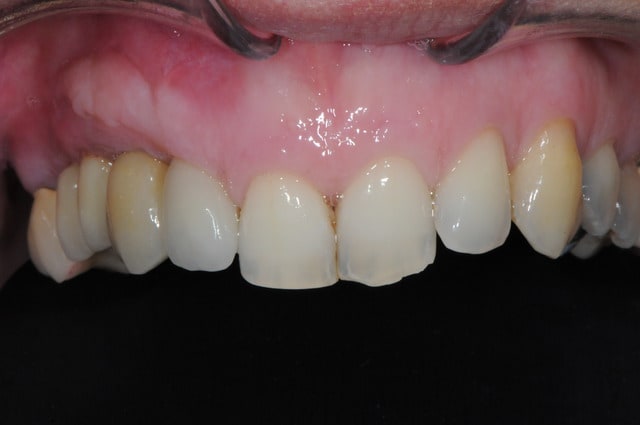

Patiente présente une perte alvéolaire de la table externe suite à fracture radiculaire.

J'ai réalisé un lambeau tracté coronairement mais je pense que certains auraient peut-être réalisé un lambeau conjonctif palatin.